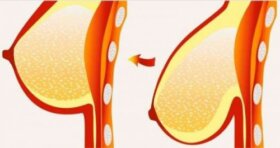

가슴은 모양이나 크기에 상관없이 여성미가 강한 신체 부위일 것이다. 시간이 지나면 자연스럽게 가슴 탄력이 줄어들지만 많은 여성이 처진 가슴을 예방하거나 바로잡는 방법을…